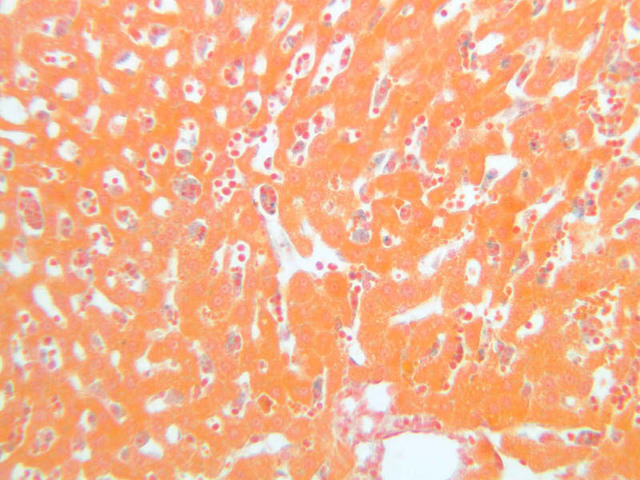

The specimen on slide B-39 was prepared by perfusing India ink into the blood stream of an animal. Examine this specimen with an eye to understanding how the capillary beds of the exocrine and endocrine portions of the pancreas differ (B-39, Ink/H&E [10x, 20x-labeled] [10x] [10x, 20x]).

9 Islet of Langerhans IL, (circled area) H&E, Ink/H&E b36 interlobular duct pancreas 10x labeled.jpgB36, Pancreas, 10x; b36 islets of langerhans pancreas 40x labeled.jpgB36, Pancreas, 40x; b39 capillary beds pancreas 20x ink he labeled.jpgB39, Pancreas, 20x

11 Capillary (none) Ink/H&E b39 capillary beds pancreas 20x ink he labeled.jpgB39, Pancreas, 20x